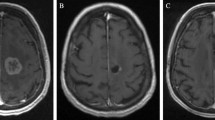

Radiographic changes after LITT can be variable but generally follow a trend of an initial increase in the size of the contrast-enhanced volume followed by a steady decrease. In the initial series published by Carpentier et al., the thermal ablation zone showed postoperative expansion of the necrotic area followed by a decrease in size [7]. Interestingly, the authors noted that the FLAIR volume did not increase postoperatively. These results are comparable in the subsequent larger series. Rao et al. reported that in the majority of targets treated (12 out of 14), the immediate postoperative volume had an average increase to 2.78 times the preoperative volume [9]. Thereafter, some treated areas continued to increase in size up to 2–4 weeks, followed by a gradual decrease in size. The majority of these treated areas returned to their preoperative sizes by 16 weeks. Chaunzwa et al. found that at 6 weeks, the contrast-enhanced volume showed a median increase in the volume of up to 34%, but this was associated with a median reduction in FLAIR volume of 36% [11]. At 3 months, the contrast-enhanced volume largely returned to their preoperative baseline, but the FLAIR volume continued to decrease to 74% of the baseline volume. At 6 months, the contrast-enhanced volume showed a decline in size compared to the preoperative volume, with an overall median reduction of 34%. The median FLAIR reduction was 77% at this time point. Beechar et al. reported similar response, with the median post-contrasted volume increase at 3 months, followed by a decrease at 6–9 months post-LITT [18]. Similarly, the FLAIR volumes at 6 months demonstrated significant reduction compared to pre-treatment volumes. Figure 5.5 showcases an example of imaging changes after LITT.

Contrast-enhanced T1W imaging in a patient with metastatic melanoma showed no significant change in the contrast-enhancing lesion size on preoperative imaging (a) and postoperative imaging at two weeks (b), but a significant reduction in associated FLAIR volumes between preoperative imaging (c) and postoperative imaging (d)

Compared to these series, Smith et al. reported a similar increase in volume followed by a decrease, but the trend observed in this study appeared to be on a longer time course [12]. Most notably, an increase in the lesional volume was observed in the majority of patients all the way up to their 6-month follow-up, and the volume reduction only began to be observed in the majority of the patients at 12 months. One explanation here may be that this study included patients with both primary and secondary brain tumors failing radiosurgery as opposed to metastatic in-field recurrence alone. The degree and timing of FLAIR signal resolution has also not been well studied or well stratified by pre-LITT lesional sizes. Whereas no significant associations were found with these factors in the LAASR study [5], Beechar et al. found that the smaller preoperative volumes respond better radiographically than those with larger volumes [18]. The authors postulated that this may be because of residual tumor cells that may be left unablated in patients with larger tumor volumes.

Overall, these results cautioned against interpreting LITT failure as an increase in the lesional volume alone. As these studies would suggest, capturing imaging changes at an early time point could lead to an inaccurate interpretation that the treatment has failed. Treatment response may be more accurately represented by a trend in the lesional volumes and the FLAIR volumes over time.